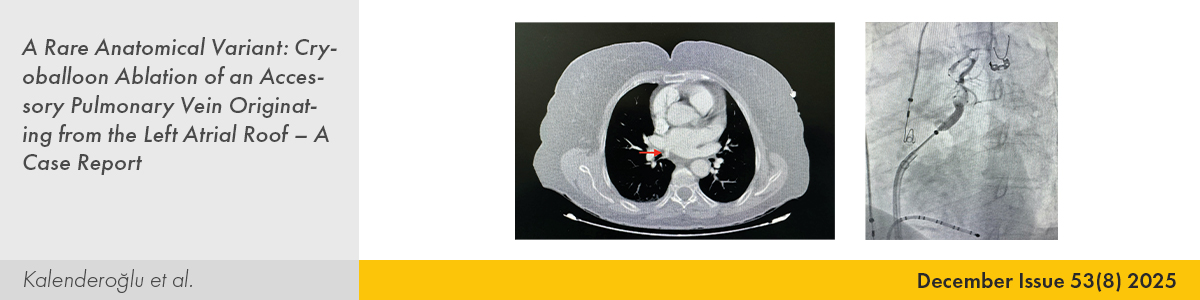

| CASE IMAGE | |